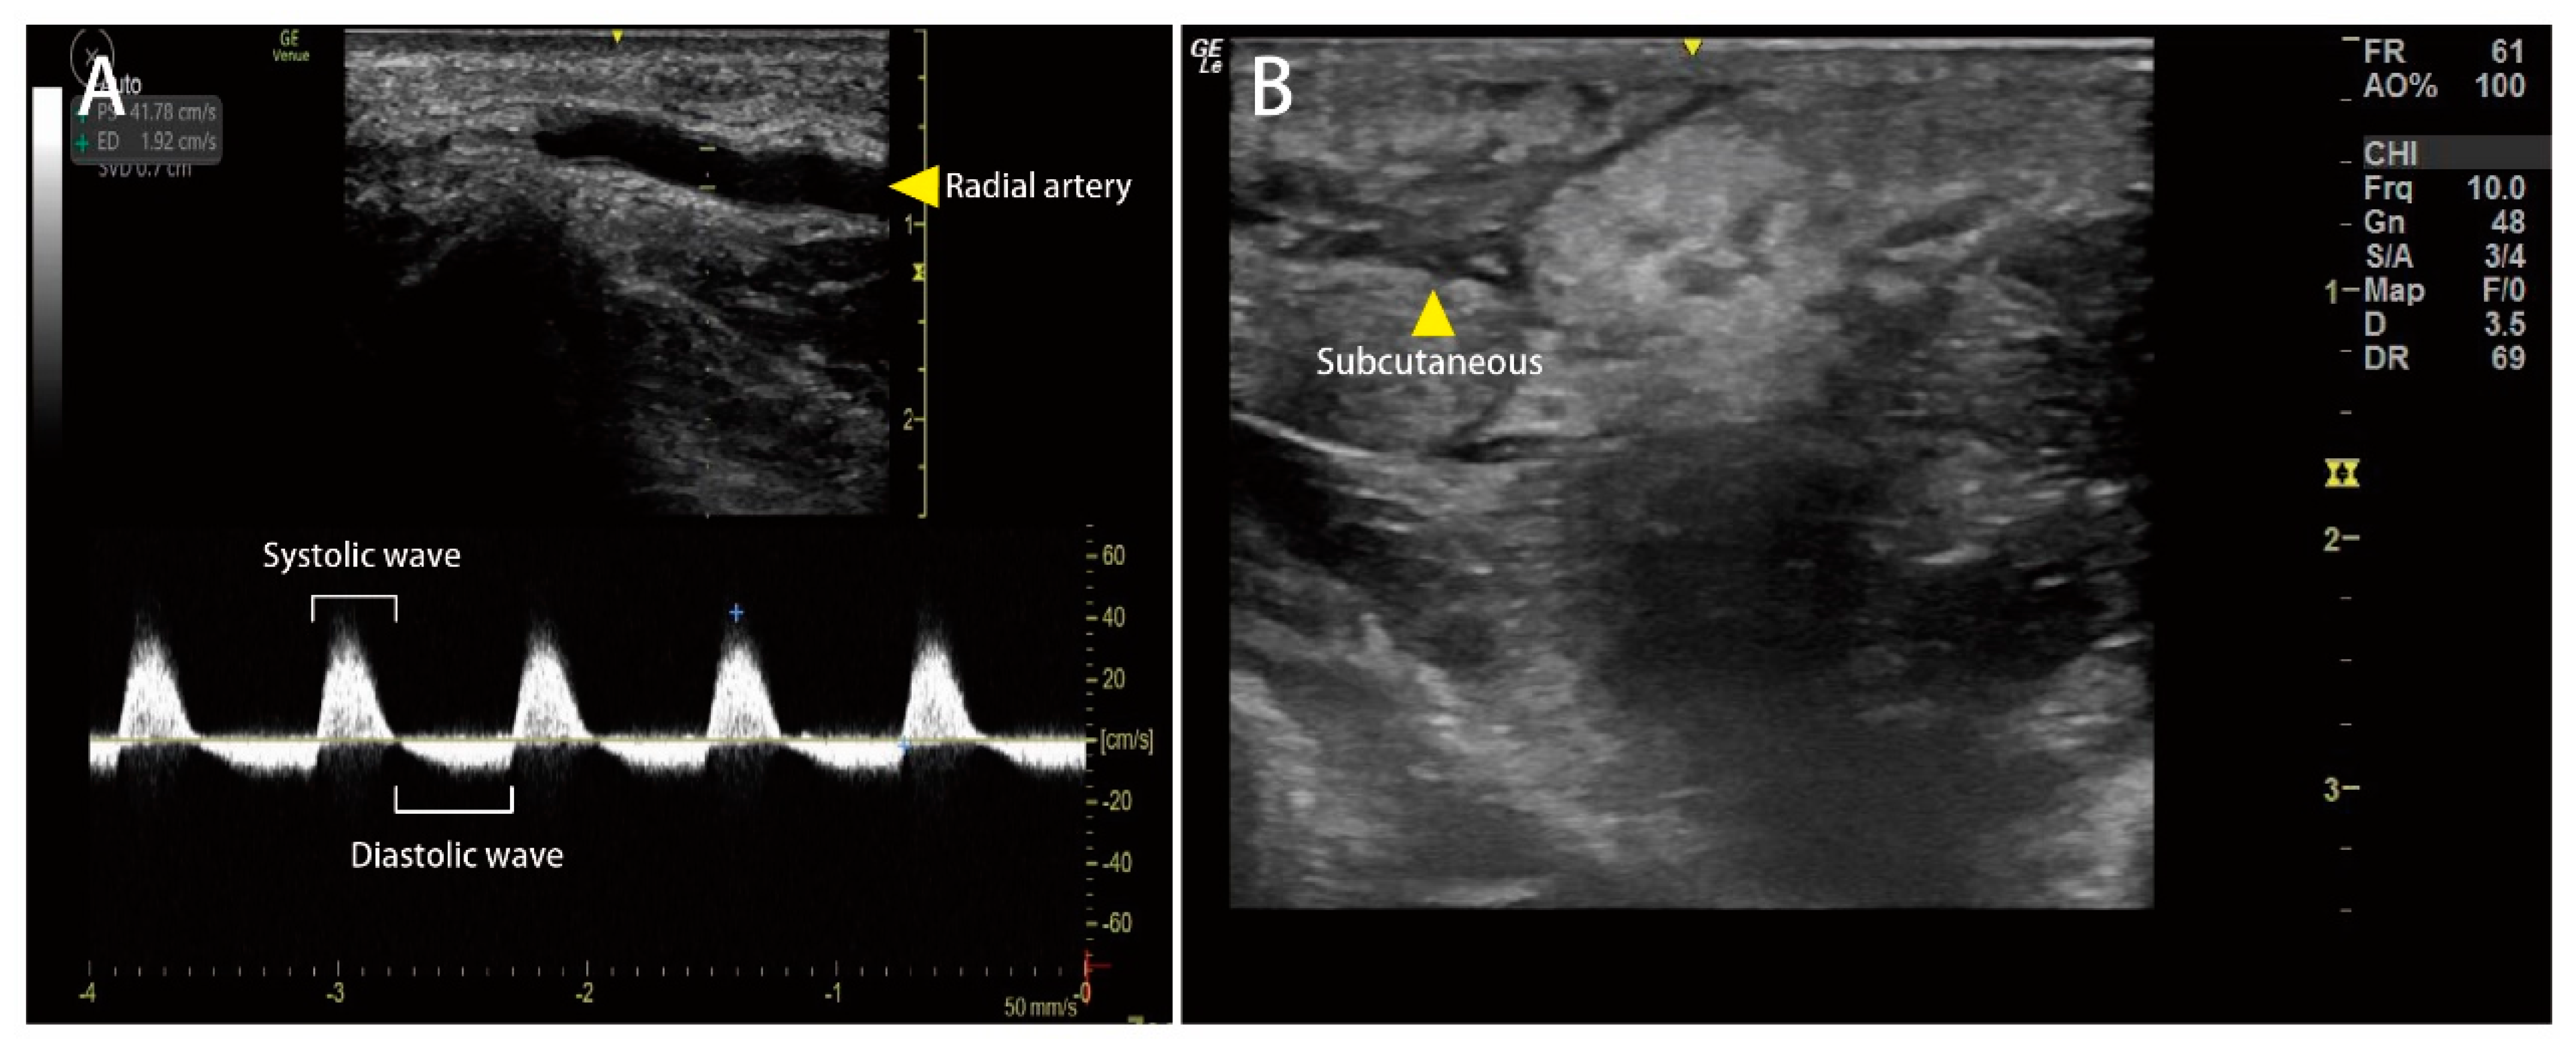

Prediction of Compartment Syndrome after Protobothrops mucrosquamatus Snakebite by Diastolic Retrograde Arterial Flow: A Case Report